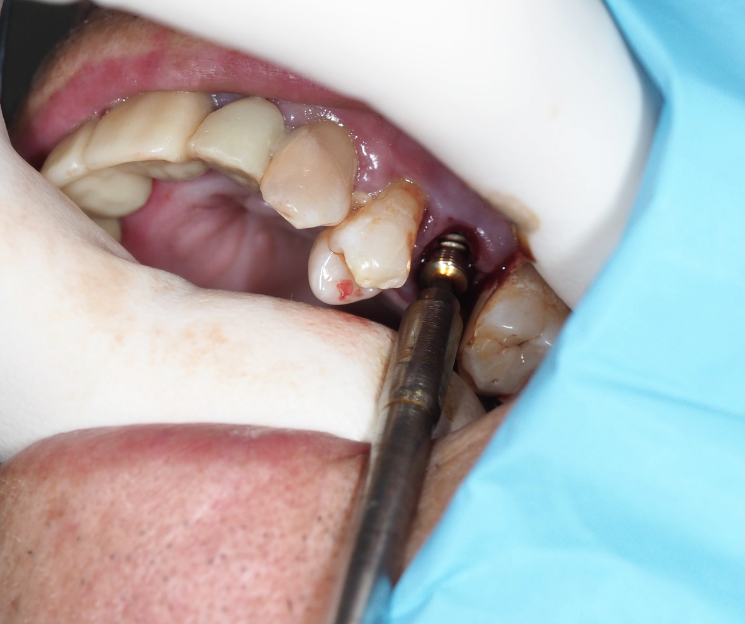

Extracción e inserción inmediata:

- Extracción atraumática: Se realizó la exodoncia del diente 25, preservando al máximo las estructuras óseas.

- Colocación del implante: Se procedió a la inserción del implante monofásico compresivo en el mismo acto quirúrgico.

- Estabilidad: Gracias a la condensación ósea lograda, se obtuvo una fijación óptima que permitió la carga inmediata.